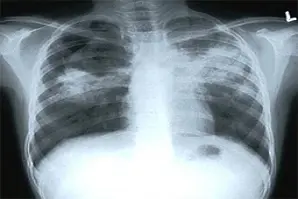

Датата на Международния ден не е избрана случайно. В същия ден през 1895 г. немският физик Вилхелм Конрад Рьонтген изследва и документира електромагнитно излъчване, което днес носи името му, а самият той го нарича „Х лъчи”. Революционното му откритие го прави носител на първата Нобелова награда за физика през 1901 г. и основоположник на съвременната образна диагностика. Това е една от най-прогресивните дисциплини в областта на медицината. Тя представлява съвкупност от различни по вид неинвазивни изследвания, спомагащи за графичното изобразяване на вътрешни органи в човешкото тяло. Този тип технологии са неразделна част от клиничното диагностициране и някои физиологични изследвания. Използват се и по време на инвазивни операции.

Първоначално, необходимата образна медицинска информация за правилна диагностика и лечение се е събирала чрез използване на  йонизиращи лъчения (рентгенови лъчи). По-късно се въвеждат и други подходи за получаване на медицински изображения, като в наши дни, след завършването на задължителен стаж, рентгенолозите, рентгеновите лаборанти, радиолозите и професионалистите от сродни области могат да работят с разнообразна апаратура. Съвременните диагностични и терапевтични методи на образната диагностика включват: магнитно-резонансната томография, позната като ядрено-магнитен резонанс (ЯМР); рентгенография и рентгеноскопия, компютърната томография, медицинската ехография и др.